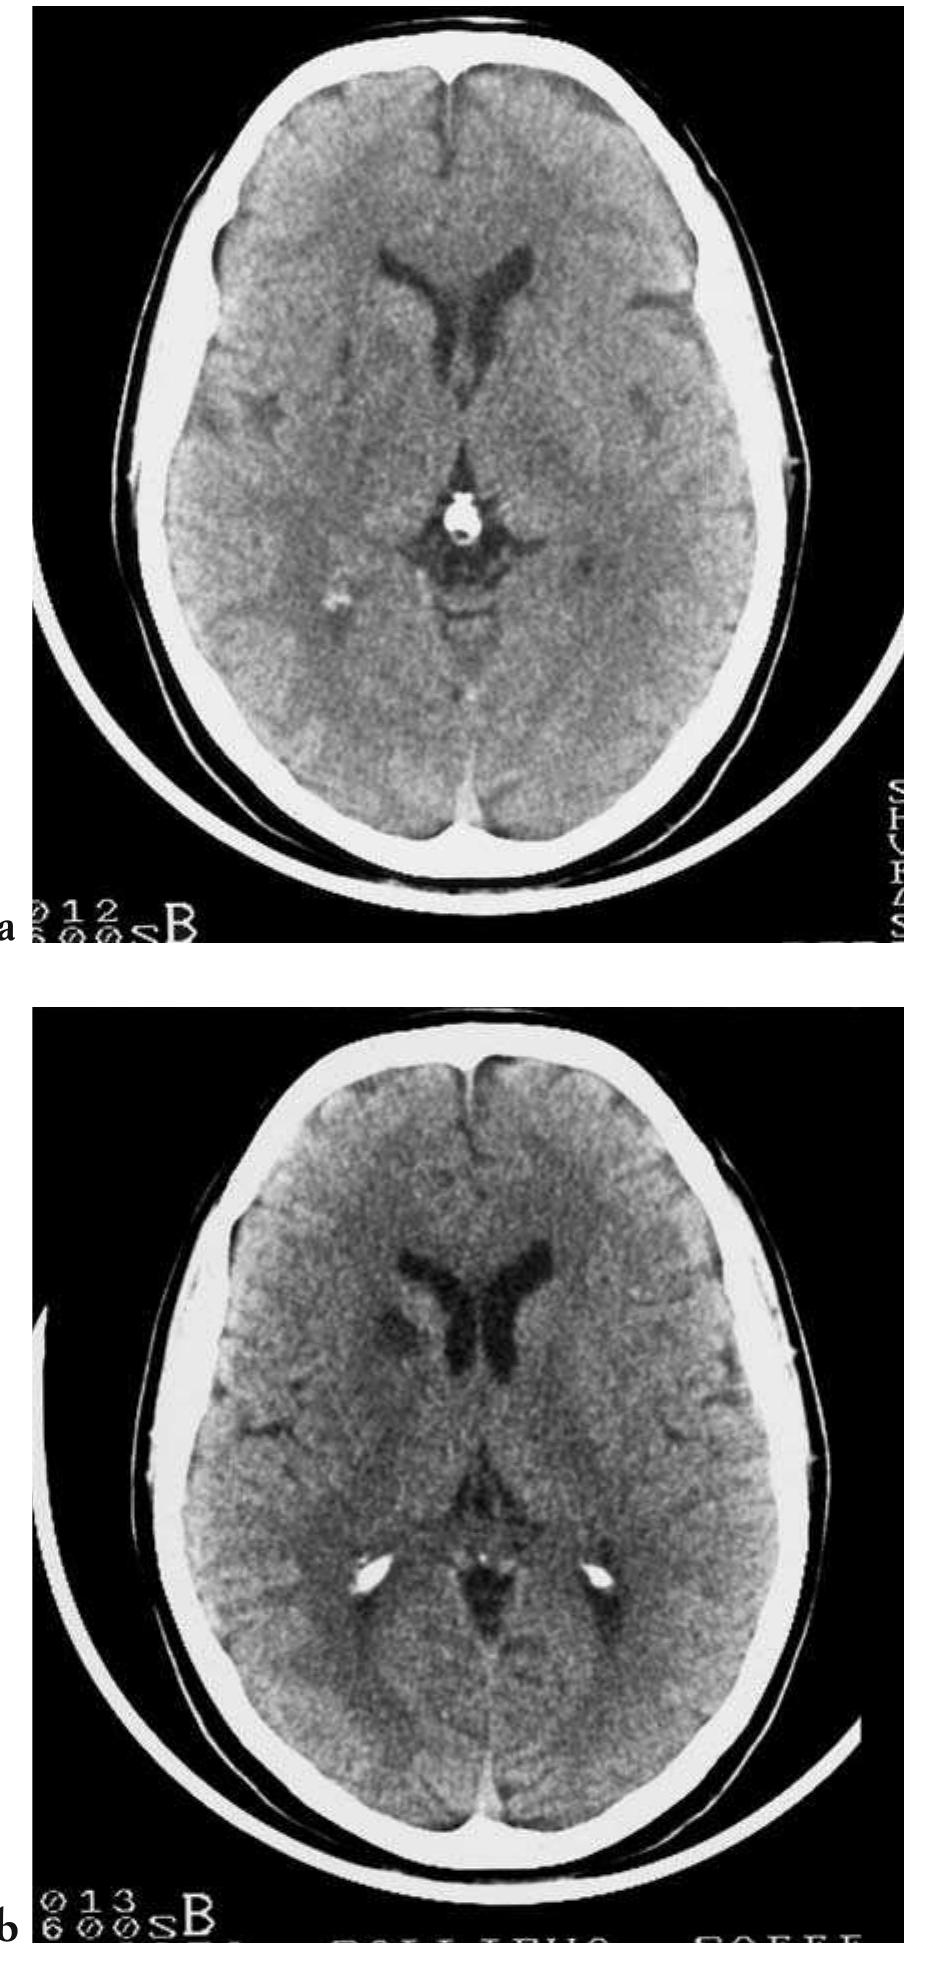

![— CT is the preferred method of imaging in co- ma patients due to its very rapid examination acquisition speeds, with single or multiple slice scanning times faster than one second in latest generation appliances; in addition to its gener- al diagnostic capabilities, it is also very sensitive in recognizing acute and hyperacute phase in- tracranial haemorrhages, in localizing the cra- nial compartment of the bleed (e.g., subdur- al/epidural, subarachnoid, intraparenchymal); finally it is almost universally available in the Fig. 4.17 - Acute hydrocephalus in a case of spontaneous subarachnoid haemorrhage. Unenhanced cranial CT shows an intra- ventricular blood clot at the level of the foramina of Monro and the symmetrical subarachnoid haemorrhage. Also note the di- latation of the lateral ventricles, including the temporal horns, as a consequence of the obstructive hydrocephalus. [a-c) unen- hanced axial CT]](https://figures.academia-assets.com/35610716/figure_279.jpg)